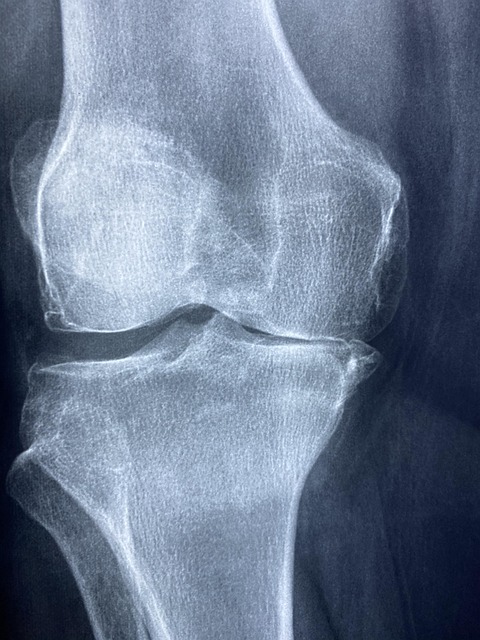

콘드로이친은 연골의 중요한 구성 성분 중 하나로, 연골 세포가 수분을 유지하고 충격을 흡수하는 역할을 합니다. 이 성분은 관절에 충분한 수분을 공급해 연골이 마르고 손상되는 것을 예방하며, 관절을 원활하게 움직일 수 있도록 돕습니다. 주로 글루코사민과 함께 섭취되는 경우가 많습니다.

콘드로이친은 퇴행성 관절염(특히 무릎 관절염)의 증상 완화에 도움을 줄 수 있습니다. 연구에 따르면, 콘드로이친은 연골의 파괴를 늦추고, 연골 복원을 촉진하여 관절 통증을 줄여주는 효과가 있습니다. 주기적인 복용을 통해 움직임의 자유로움과 통증 완화를 경험할 수 있습니다.

연골은 시간이 지나면서 자연스럽게 마모되고 퇴화됩니다. 콘드로이친은 연골을 재생시키고 강화하는 데 도움을 줍니다. 따라서 관절의 유연성과 움직임을 높이는 데 중요한 역할을 합니다. 고령층, 무릎이나 엉덩이 관절에 부담이 많은 사람에게 매우 유익한 성분입니다.